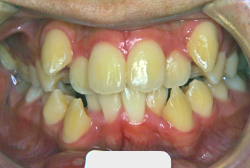

叢生(そうせい)

凸凹な歯並びのことを叢生といいます。矯正歯科に来院する患者様の主訴の中で、最も多いのが「配列の凸凹を真っ直ぐにしたい」というものです。歯の大きさと顎の大きさの調和がとれていないことが原因です。

凸凹を主体としたケースの場合、当院の平均治療期間は18ヶ月ですので、このケースは少し長めに経過しました。理由の一つは凸凹の程度がかなり重症だったと言うことですが、もう一つは、右下第2大臼歯が45度くらい前傾していたため、それを整直化させるために時間を要したと考えています。いずれにしても最終結果は大変よい状態と思います。

治療前は並びが乱れて見た目が悪いというのはもちろん問題ですが、歯科医学的に一番困るのは噛み合わせが悪いという点です。上下の犬歯(3番目の歯)は、上下的に離れた位置にあるため接触することができません。つまり歯としては存在していても、歯としては機能していないということです。